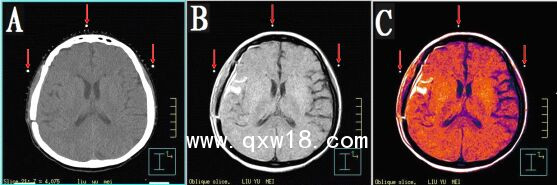

本產(chǎn)品主要適用于不同模態(tài)圖像引導(dǎo)下放療時(shí)定位,定點(diǎn)經(jīng)皮穿刺活檢或積液抽吸引流,不同模態(tài)間圖像融合控制點(diǎn)配準(zhǔn)等。

3.??同一定位貼,在多種模態(tài)掃描下成像均能顯示為點(diǎn)狀,可用作圖像融合的共同配準(zhǔn)控制點(diǎn),大小、位置一致,方便全身或軀段臟器異機(jī)圖像融合,精度高,易開展新的臨床應(yīng)用。

CT和MR通用型:具有同一個(gè)定位球在CT掃描高密度、MR常規(guī)掃描高信號(hào)的特點(diǎn),主要用于

CT/MR圖像融合,更換掃描設(shè)備,不需要更換標(biāo)記點(diǎn)。型號(hào)MK⊙CT/MR,每盒三貼;